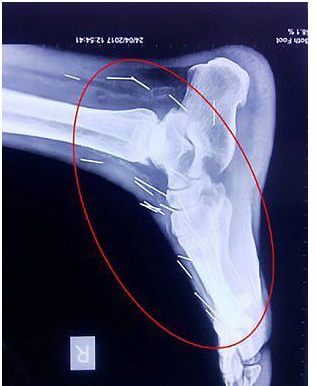

据英国《每日邮报》5月1日报道,近日,印度北部拉贾斯坦邦科塔市的56岁男子米纳(BadrilalMeena)到医院为脚趾进行常规手术,但医生在他的X光检查中发现他的脚、手臂和喉咙中发现75根针,米纳表示不知道原因,医生诊断为针明显是被故意插入体内的。

米纳在当地的一家铁路公司工作,他的家人也对事件毫不知情,迄今为止,他们问诊的所有医院中没有一间愿意做手术把针取出,75根针中有40支根于喉咙、25根在右腿、2根在手臂。米纳被迫只能在孟买的病床上等待。